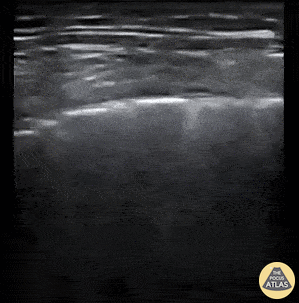

Patient presented to the Emergency Department with 2-day history of worsening dyspnea and increased work of breathing. He was profoundly hypoxic upon arrival with EMS (O2 sat on 2L via nasal prongs was 42%; improved to 75% upon switching to high flow nasal cannula at 40L/min). A 12-zone lung ultrasound was performed using a linear probe and what is pictured is from L6 (left inferior posterior zone). You can appreciate the coarse irregular pleura, patchy B-lines, and and small areas of consolidation. Findings are typical for clinically-suspected COVID-19 pneumonitis. Cian McDermott, Emergency Physician; Dublin, Ireland @cianmcdermott